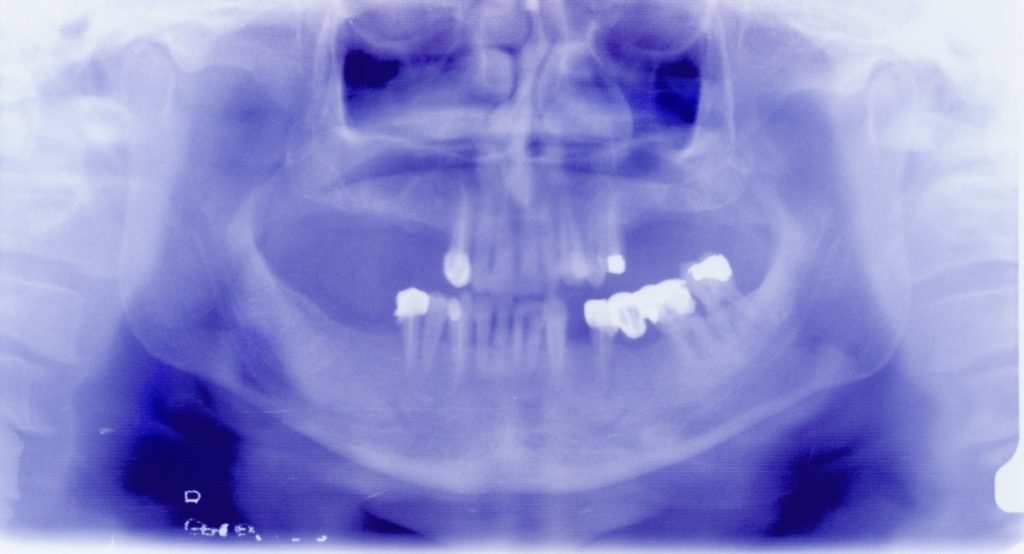

Follow-up panoramic radiograph following installation of the lower implants and removal of the lower left wisdom tooth.